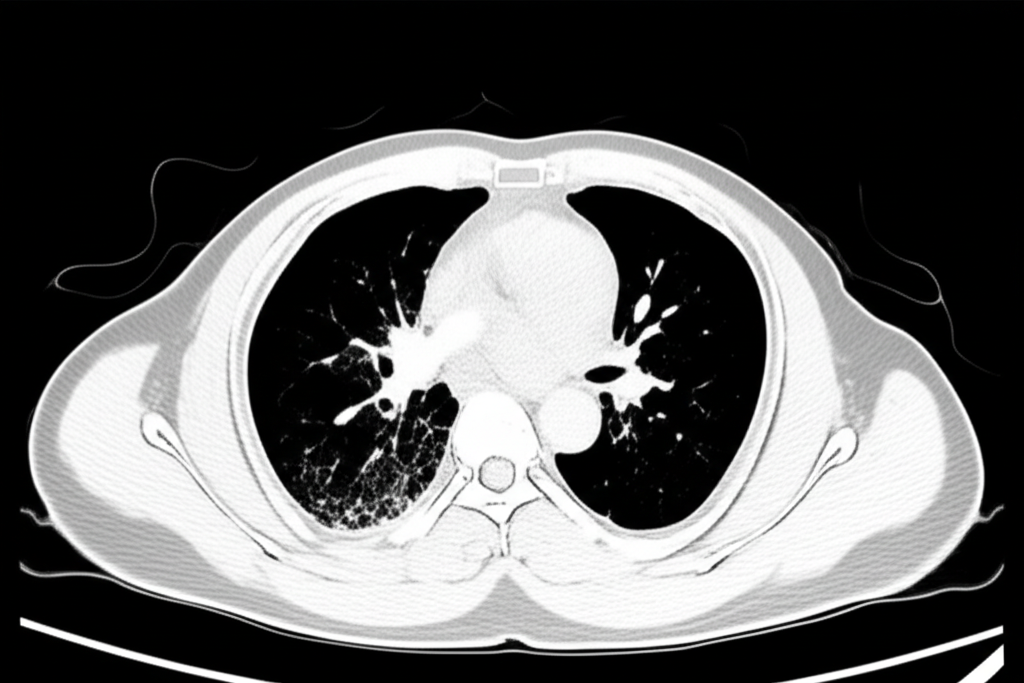

폐 CT는 폐 질환 진단에 매우 중요한 역할을 하는 영상 검사입니다. 흉부 X선 검사보다 훨씬 더 자세한 정보를 제공하여 폐암, 폐렴, 만성 폐쇄성 폐질환(COPD) 등 다양한 질환을 조기에 발견하고 정확하게 진단하는 데 도움을 줍니다. 건강 검진 시 폐 CT 검사를 고려하는 것은 건강한 삶을 유지하는 데 매우 현명한 선택입니다.

폐 CT로 알 수 있는 것은 폐암뿐만 아니라 폐렴, 결핵, 기관지확장증, 간질성 폐질환 등 다양한 폐 질환을 진단하는 데 유용합니다. 이러한 질환들은 호흡 곤란, 기침, 가래 등의 증상을 유발할 수 있으며, 심한 경우 생명을 위협할 수도 있습니다. 폐 CT 검사를 통해 이러한 질환들을 조기에 발견하고 적절한 치료를 받으면 질병의 진행을 늦추고 합병증을 예방할 수 있습니다.